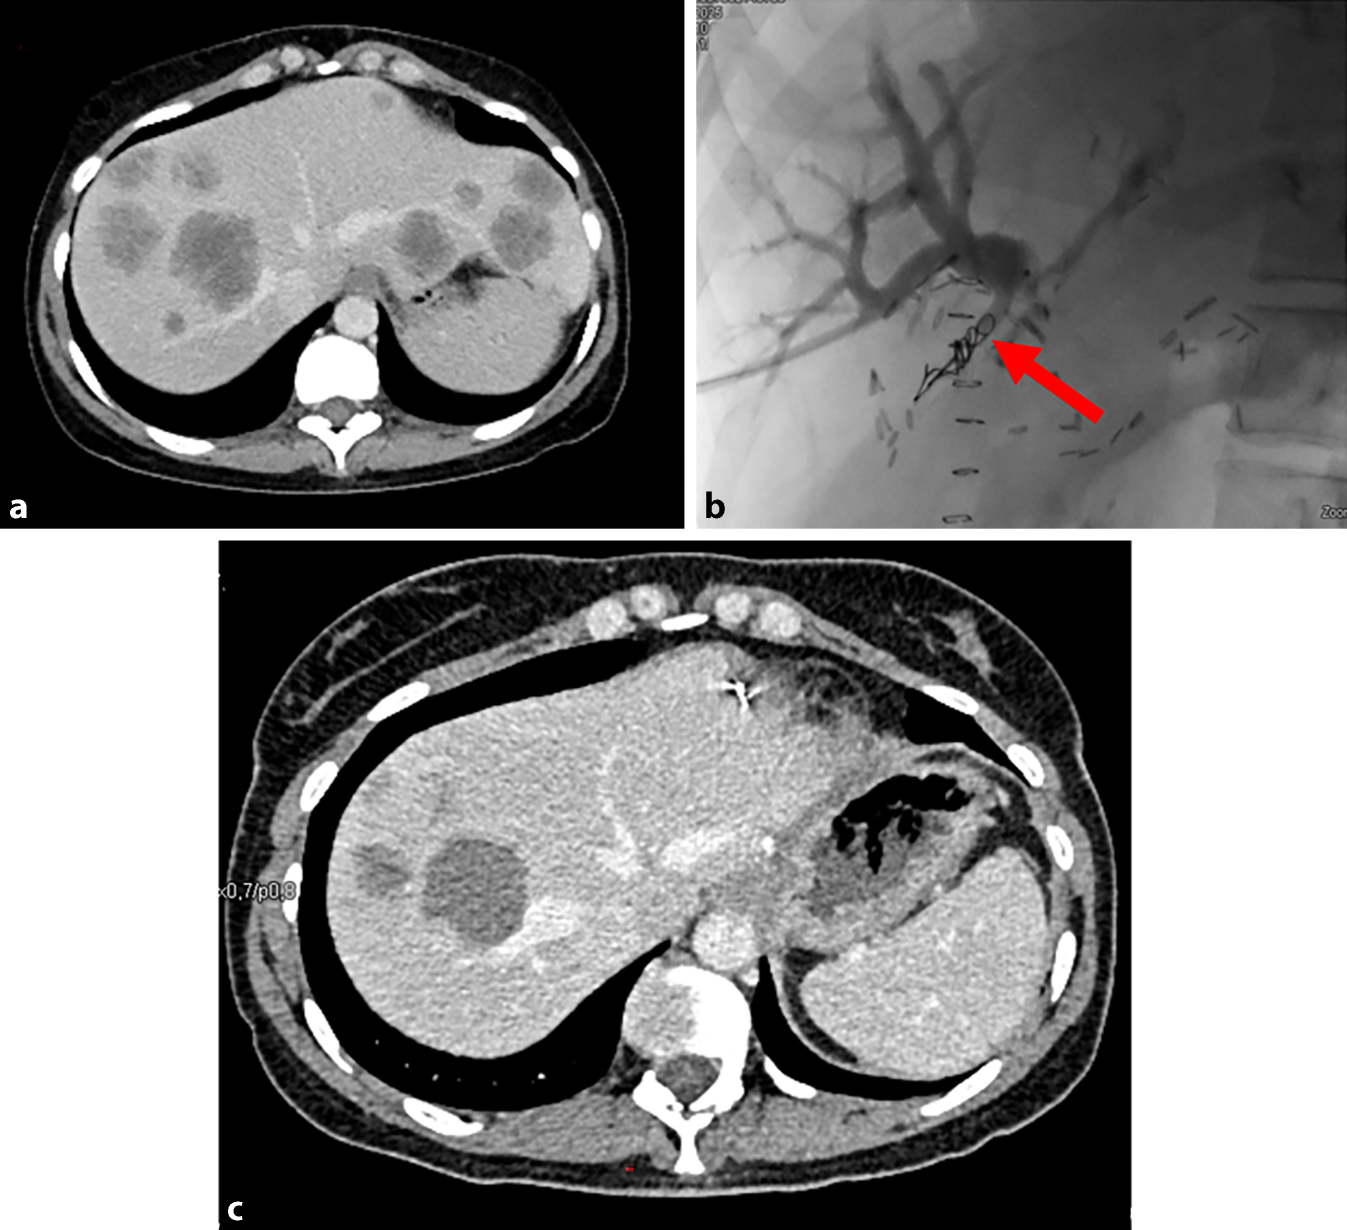

Abb. 1

Mehrzeitige Lebersanierung bei 42-jähriger Patientin mit synchron metastasiertem Sigmakarzinom. Zunächst Resektion des Primarius, gefolgt von Chemotherapie (6 Zyklen FOLFOX + Bevacizumab). Hierunter partielle Remission. Nach 3 Monaten atypische Resektion S II/III und S IVa/b. 1 Woche später Portalvenenembolisation (PVE) rechts. 6 Wochen später Hemihepatektomie rechts. a Leber bei Erstdiagnose mit diffuser Metastasierung. b PVE rechts, roter Pfeil auf den Coils in situ des rechten Pfortaderastes. c Ergebnis nach PVE und Sanierung des linken Leberlappens vor geplanter Hemihepatektomie rechts. (Mit freundl. Genehmigung, © Klinik für Radiologie und Nuklearmedizin, Universitätsklinikum Mannheim)